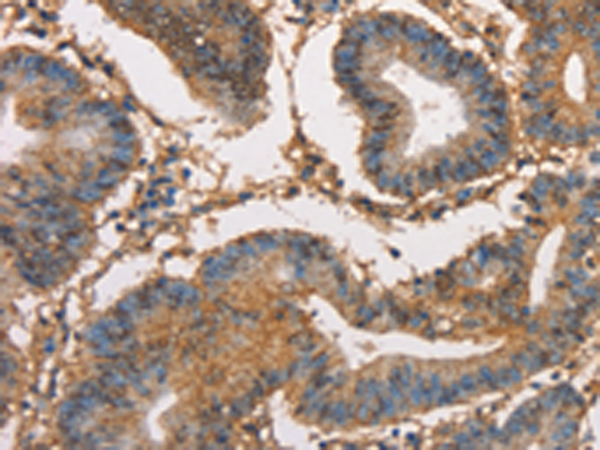

分类: 科研抗体货号: P07985别名: HXK3; HKIII应用: IHC反应种属: Human, Mouse, Rat